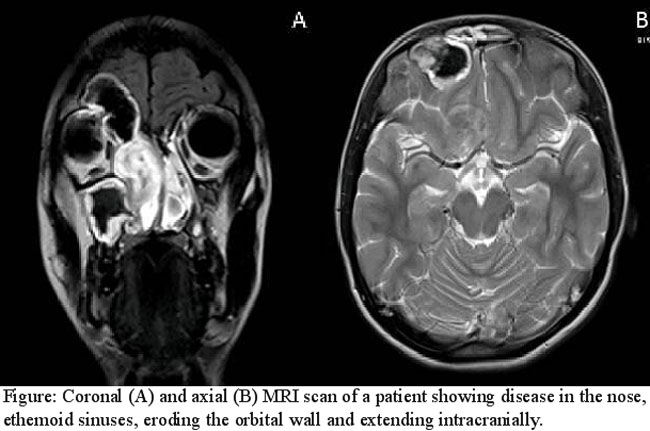

MRI showed abnormal signal intensity material and mucosal thickening with expansion in maxillary, ethmoid, sphenoid and frontal sinuses bilaterally. The imaging was suggestive of fungal infection. There was evidence of extra dural intracranial extension in the region of right frontal sinus along with involvement of the lamina papyracea and medial wall of the orbit on the right side. The orbital fat and muscles were intact bilaterally (Figure).